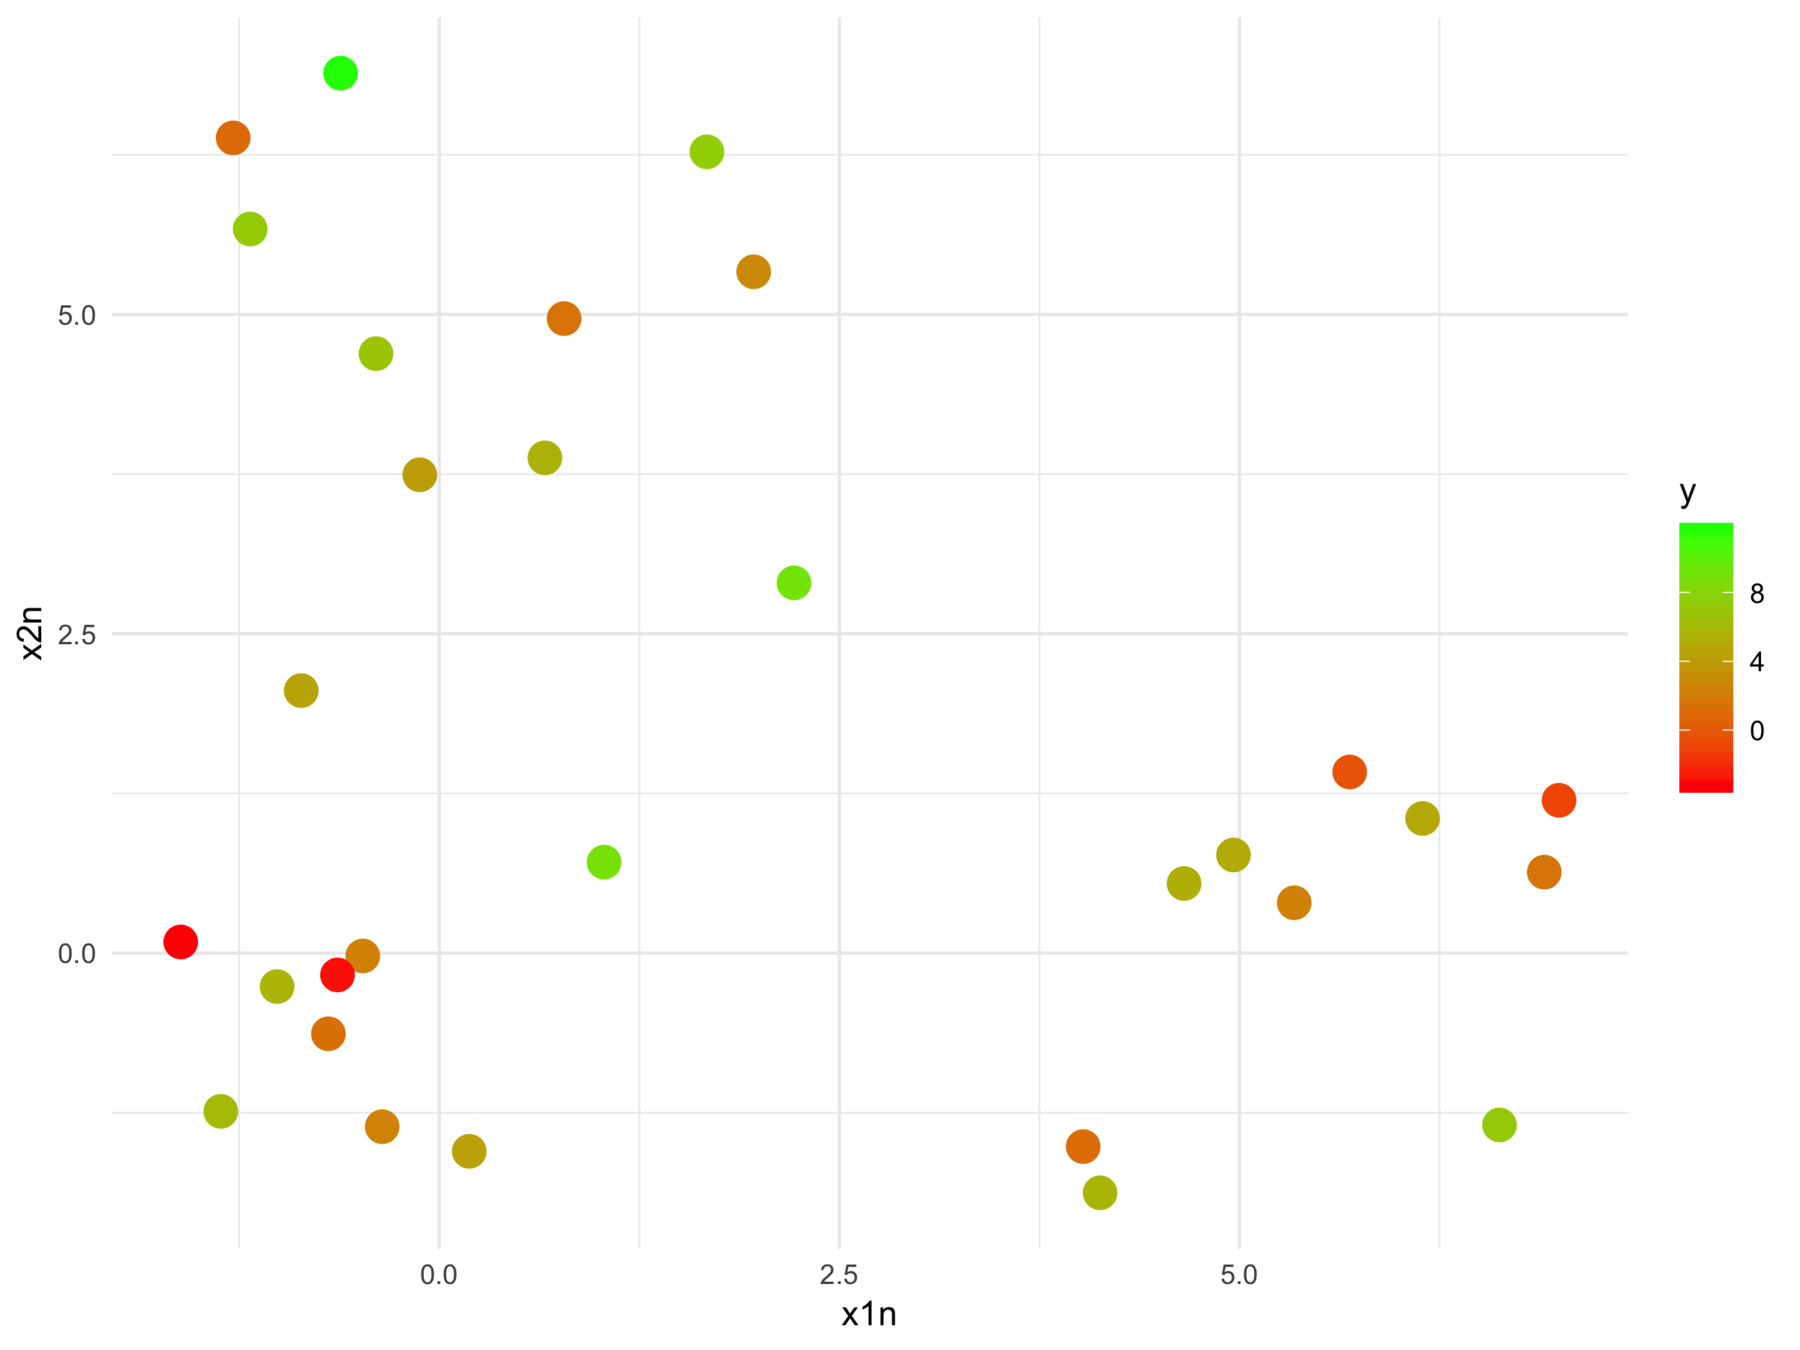

F-statistic: 24.7 on 2 and 28 DF, p-value: 6.572e-07We can't tell this

from this

The model fits relationships between the regressors and the outcome

But we may want the relationships between the regressors with respect to the outcome

Construct \(h = f \circ g_y \) such that \(g_y : \mathcal{X} \rightarrow \mathcal{X'} \) is a latent space projection of the original data, whose geometry is dictated by the response.

\(X_Y = XV \tilde \Gamma\) represent the data in the latent space

Each column whose corresponding slope coefficient is not zero, contributes equally to the estimate of \(Y\) in expectation